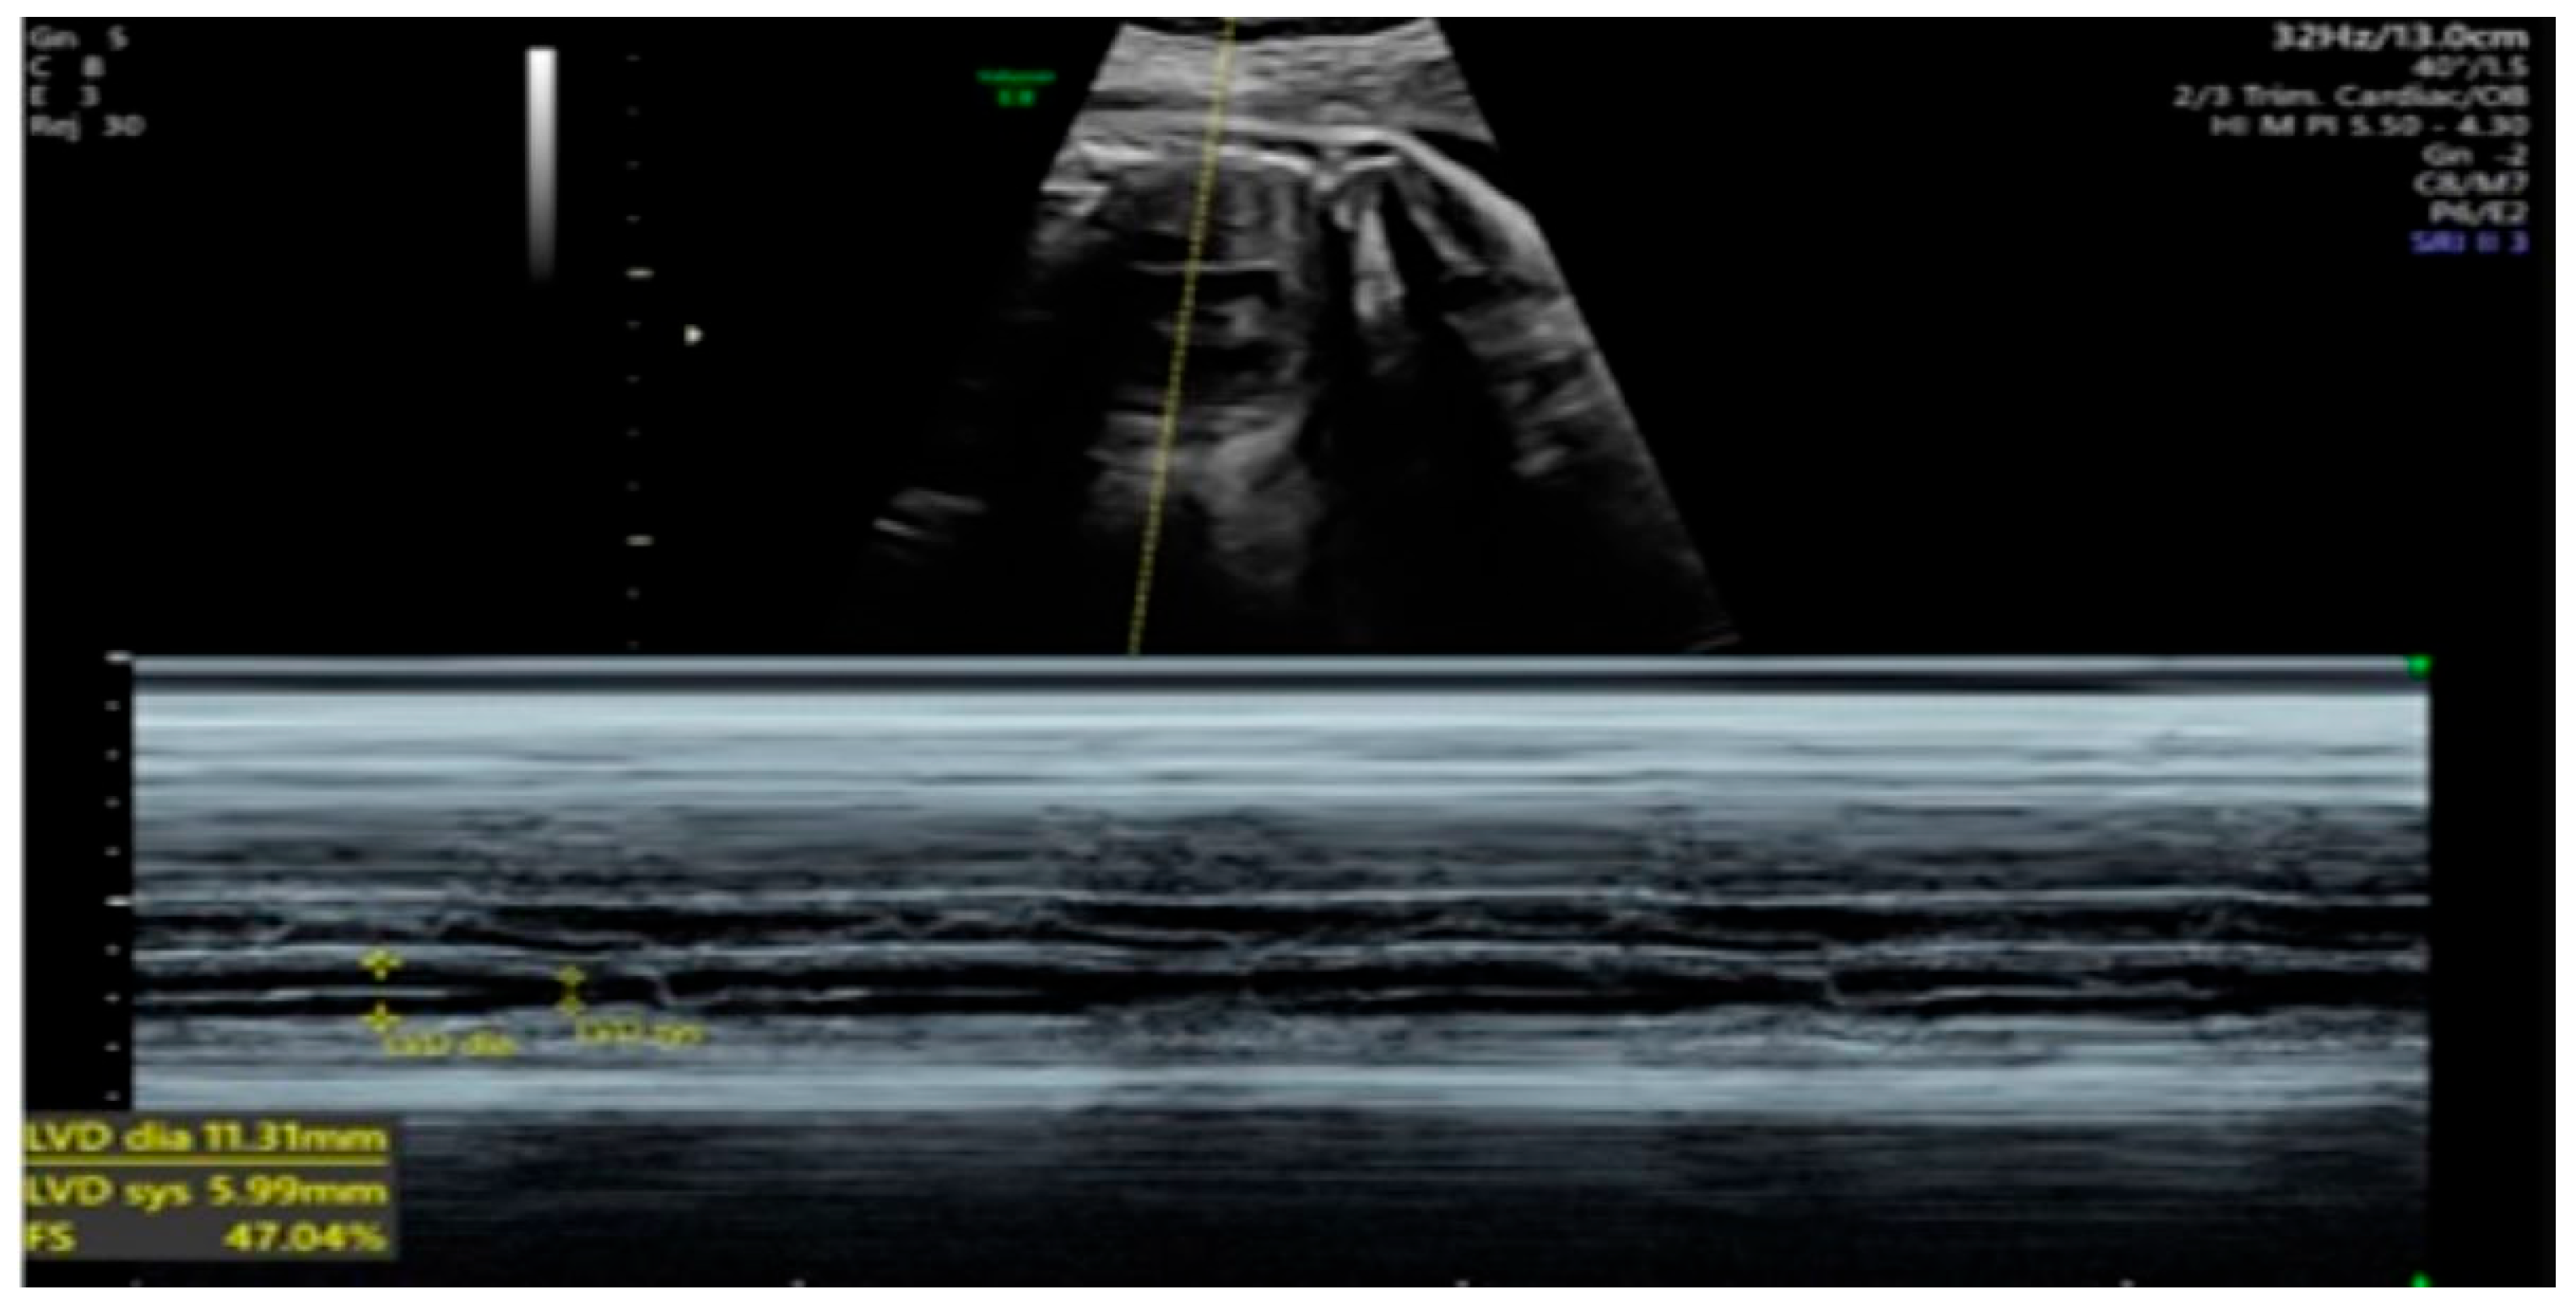

| 26 + 0 | Start of dexamethasone 4 mg/day | 60 | SF increased from 34% to 47%, but qualitative contractility decreased | Mild edema; no beta- agonists used |

| 28 + 0 | First IVIG cycle (65 g total) | 75 | SF increased to 52%; mild improvement in contractility | Initiated due to signs of fibroelastosis |